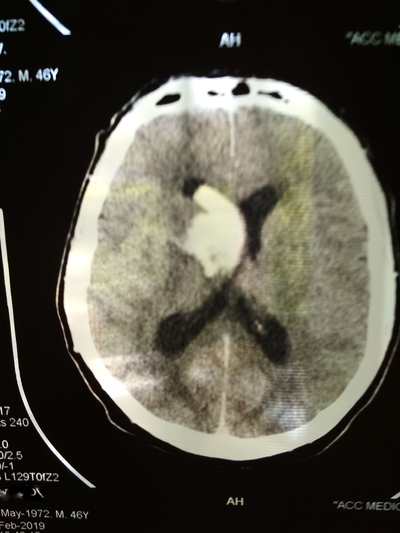

День не помню, возможно 1-2 марта, открываю глаза, а вокруг суета и непонятная обстановка. Осознаю что я а больнице, меня перетягивают с кровати на носилки и куда-то катят и тащат, укрыли сверху одеялом, внесли на улицу, очень холодно. Притащили (по другому не назовешь) меня на компьютерную томографию, перекинули с носилок на стол КТ, голову уложили в ячейку для головы и чем-то расклинили, чтобы не шевелился, больно капец. Я уже осознал что нахожусь в больнице, но что произошло не могу понять, да и думать мне было очень больно в голове.

Вернули меня в палату, перекинули на койку, и мои родные начали рассказывать, что 22 февраля мне стало плохо, качало, тошнило и рвало, жена подумала, что я выпил с друзьями в гараже. Потом вызвали скорую, которая померяла давление и там 290 на 160. Что то укололи. Потом возили в одну в больницу, они отказались принимать, повезли в другую. Вот так с 26 февраля я оказался в "еврейской", это у нас так называют гкб1. (городская клиническая больница № 1) По компьютерной томограмме врач определил геморрагический инсульт и аневризма, вот описание что это такое:

Пример аневризмы сосудов головного мозга

После КТ со мной общался врач, видя, что я уже в сознании, трогал руки ноги, просил потянуть рукой его руку, у меня плохо слушалась правая сторона тела.

Ещё врач сказал что желудочки головного мозга заполнились вытекшей кровью и они решают или вскрывать черепушку или медикаментозно лечить.

Вот тут я пересрал, совершенно не хотел проветривать бестолковку (но обрадовался когда на снимках всё таки обнаружили мозг 😁)

Итого решение врача, медикаментозное растворение крови в голове и вымывание лекарствами, чтобы не образовалась гематома, как объяснили так и пишу.